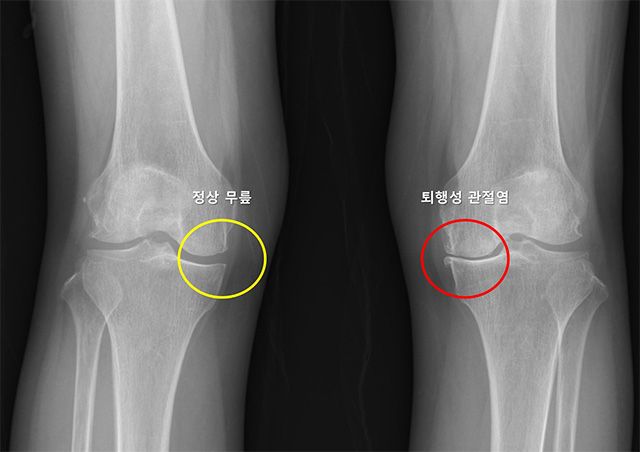

- ▲ X-ray 이미지. 정상 무릎(노란색)은 관절 간격이 잘 유지되고 뼈 모양이 정상이며, 퇴행성 관절염(빨간색)은 관절 간격이 좁아지고 뼈 모양이 변형됨. /이미지 제공=서울대병원

무릎 퇴행성 관절염은 연골과 관절 구조물이 점진적으로 손상되며 발생하는 질환으로, 통증과 운동 기능 저하를 유발한다. 전 세계 인구의 16~30%가 앓고 있으며, 고령화가 심화하면서 유병률은 꾸준히 증가하는 추세다. 특히 한쪽 무릎에 관절염이 생긴 뒤 수년 내 반대쪽에서도 유사한 증상이 나타나는 경우가 많지만, 그 진행 속도나 발생 여부는 환자에 따라 다르다.